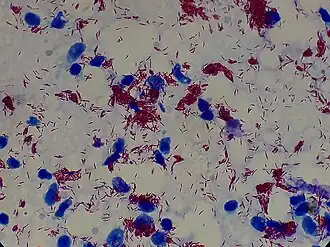

La lèpre est une infection chronique par la bactérie Mycobacterium leprae qui, comme les autres mycobactéries, est un bacille acido-alcoolo-résistant (BAAR), mis en évidence par la coloration de Ziehl-Neelsen.

La coloration de Ziehl-Neelsen permet de visualiser le M. leprae à partir de trois prélèvements[6] :